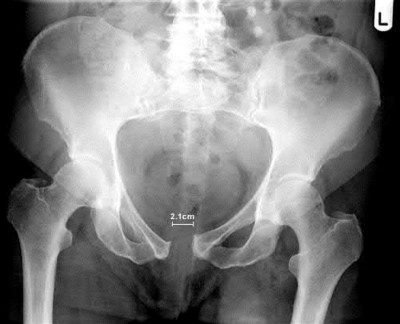

Question 5

A 13-year-old obese boy presents with 3 weeks of left groin pain and a limp. Examination reveals obligatory external rotation of the left hip during passive flexion. A radiograph is provided.

What is the recommended definitive management for a stable slipped capital femoral epiphysis (SCFE)?

Explanation

A stable SCFE is characterized by the patient's ability to bear weight (with or without crutches). The standard of care for a stable SCFE is in situ fixation with a single cannulated screw placed centrally within the epiphysis. Closed reduction is contraindicated due to the high risk of avascular necrosis.

Question 23

A 12-year-old obese boy presents with a left-sided slipped capital femoral epiphysis (SCFE).

Which of the following represents the strongest indication for prophylactic in situ pinning of the contralateral, asymptomatic hip?

The presence of an underlying endocrine disorder (such as hypothyroidism, panhypopituitarism, or renal osteodystrophy) is a strong risk factor for bilateral SCFE, with some studies reporting nearly 100% eventual bilateral involvement. Prophylactic pinning of the contralateral hip is highly recommended in these patients. Other indications include prior radiation therapy and age younger than 10.